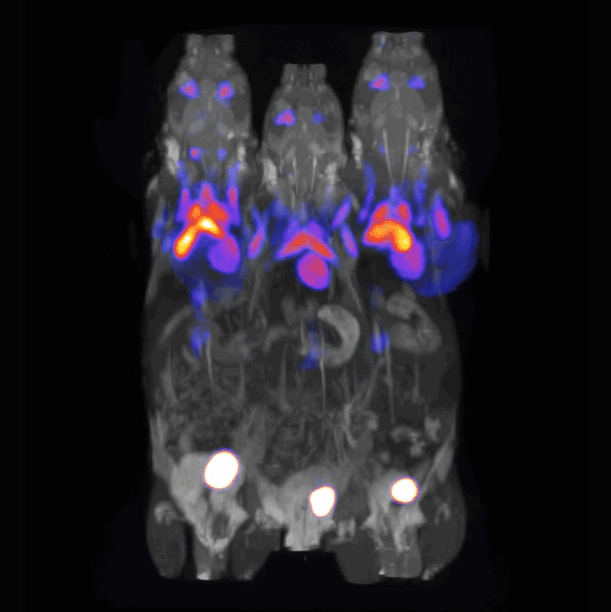

使用PET/MRI 3T设备进行的多动物成像技术

对3只携带肿瘤的小鼠同时进行扫描

〉动物模型:BALB/c小鼠

〉放射性示踪剂: 18F-FDG,剂量分别为4.87 MBq(131.6 μCi)、4.75 MBq(128.3 μCi)和5.91 MBq(159.7 μCi)

〉扫描参数: 采用GRE 3D多视野MRI技术进行扫描;采集时间为18分钟,NEX值为4,TR为10毫秒,TE为3.1毫秒,TH为0.8毫米;PET数据采用静态采集方式。

〉射频线圈:72毫米正交型发射/接收线圈。